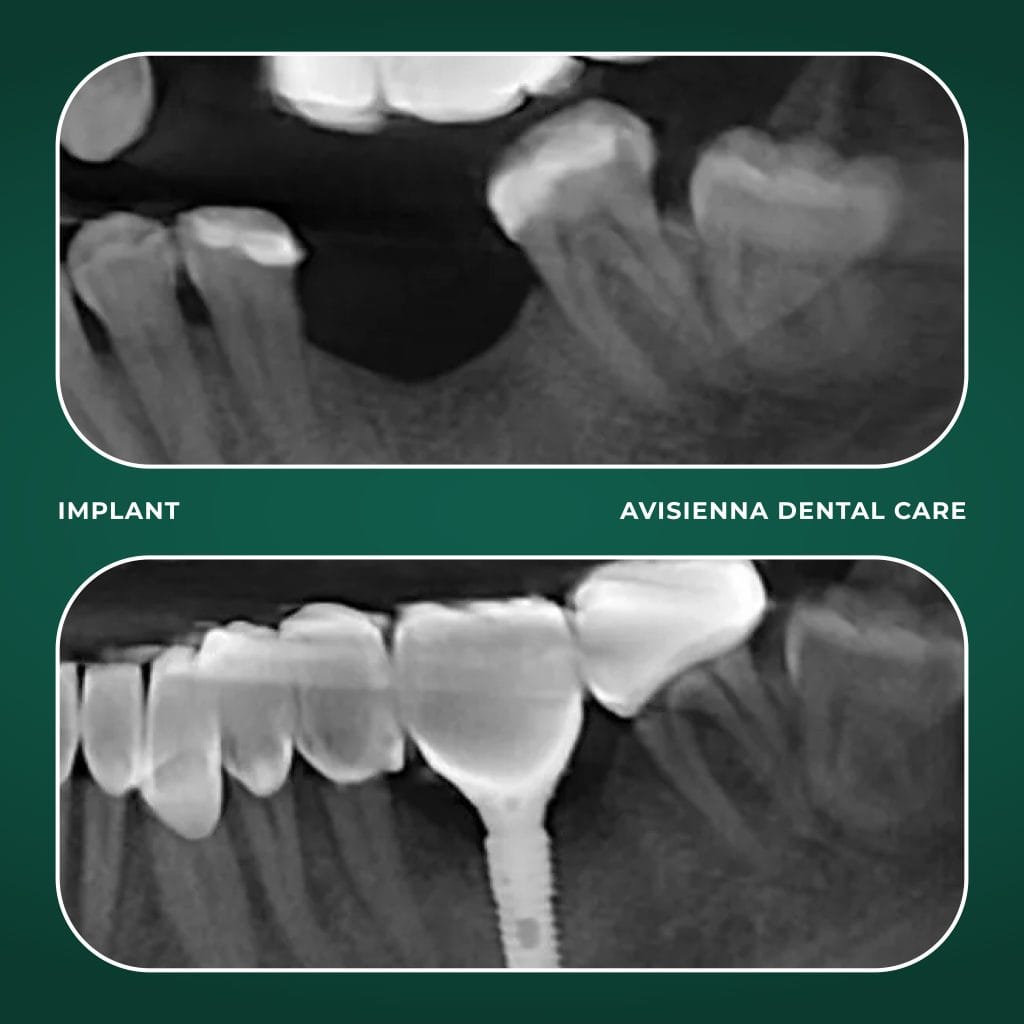

Dental implants are artificial tooth roots, typically made of titanium, that are surgically placed into the jawbone to support replacement teeth like crowns, bridges, or dentures. They serve as a long-term solution for missing teeth, mimicking the function of a natural tooth root.